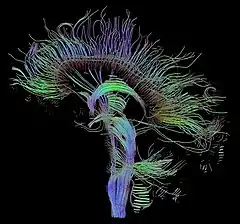

The following are images from various Medicine-related articles on Wikipedia.